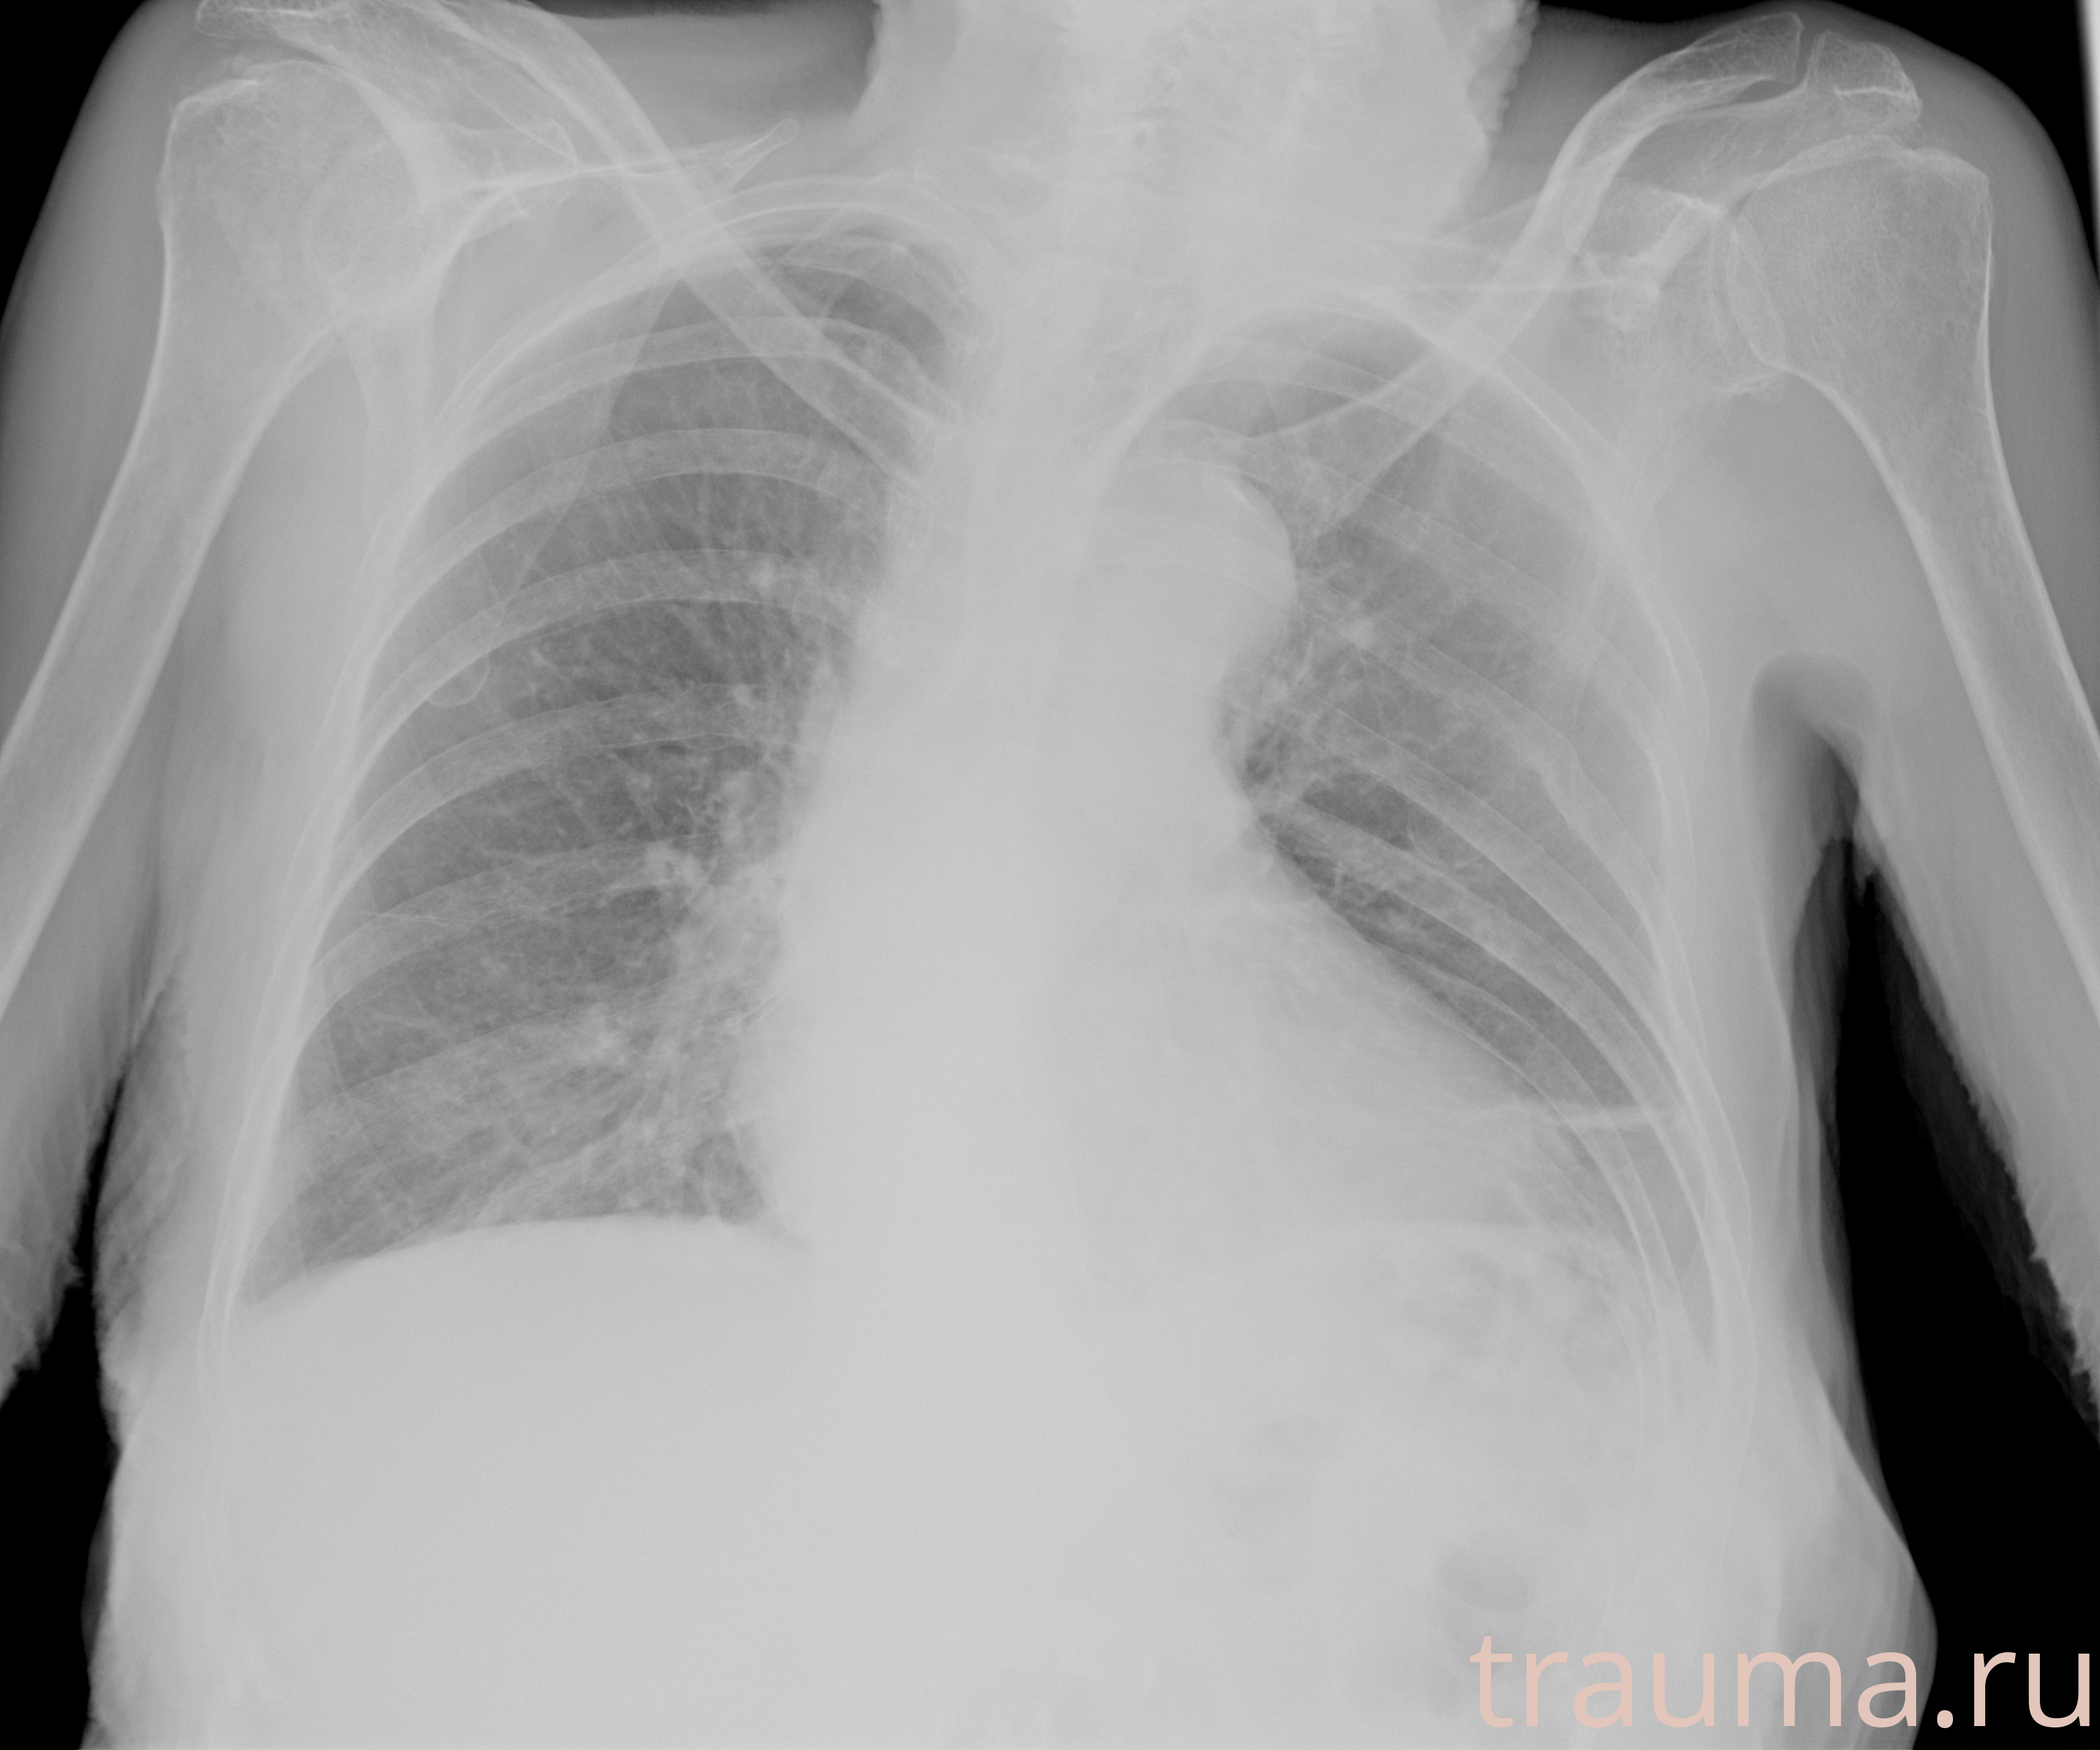

Рентген на дому: по вашему адресу приезжает врач-рентгенолог, травматолог-ортопед с мобильным рентгеновским аппаратом, проводит диагностику травмы или заболевания, делает необходимые рентгенограммы, дает рекомендации по дальнейшему лечению. Получить качественные снимки в домашних условиях возможно благодаря уникальной методике, разработанной МосРентген Центром для института  Склифосовского

при переломе шейки бедра и пневмонии от компании МосРентген Центр - партнера Института имени Склифосовского